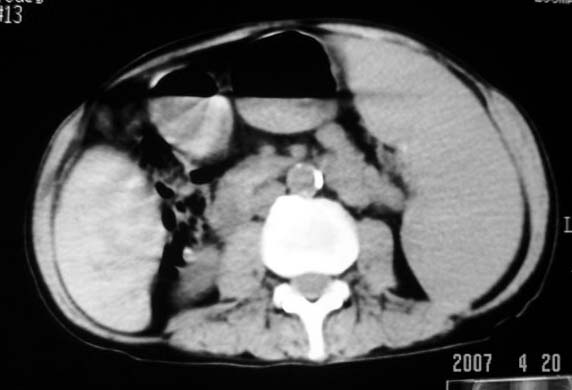

以下是引用dyqct在2007-4-20 16:38:00的发言:[br]考虑:1、巨脾;[br] 2、肝内多发低密度,首先考虑转移瘤;[br] 3、胆囊多发结石。

以下是引用andymaomao在2007-4-20 16:47:00的发言:[br]肝脾增大,肝内胆管扩张,且可见多发小囊性低密度灶,胆囊窝区高密度影,手术化疗病史,贫血....[br]1.肝脾大及贫血与术后化、药疗有关;[br]2.胆囊窝区高密度影,术后改变?肝内胆管扩张,积液?[br]3.肝内多发低密度灶,性质?建交增强